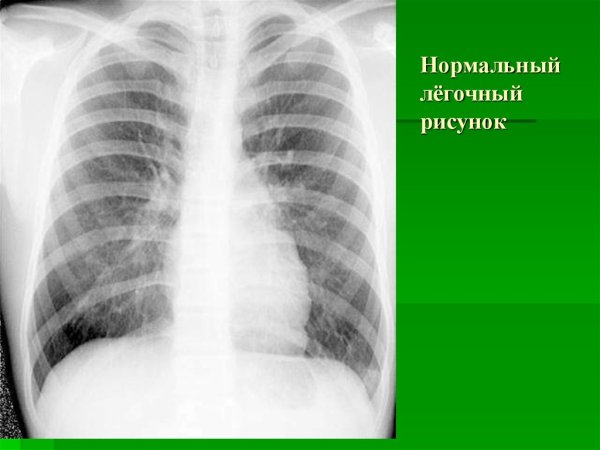

Нормальный легочный рисунок